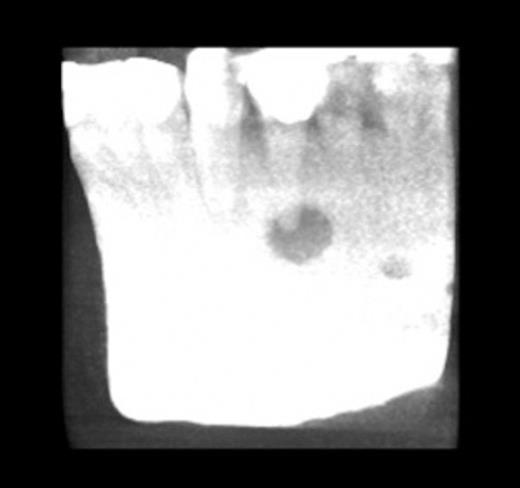

On examination there was scarring to the left mental region with evidence of previous revision surgery and a draining cutaneous sinus (Fig. 1 & 2).

showing scarring to the left mental region with evidence of previous revision surgery and a draining cutaneous sinus

Image showing scarring to the left mental region with evidence of previous revision surgery and a draining cutaneous sinus

Plain radiographs revealed a periapical radiolucency of the lower left first premolar. A gutta percha (GP) point was inserted into the sinus. Cone beam computed tomography (CBCT) showed the GP point to be in communication with the periapical area (Fig. 3 & 4).